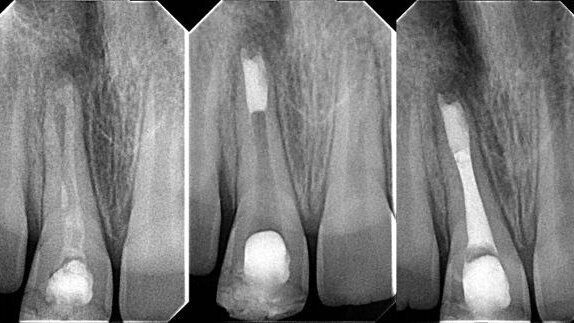

Two years ago, I was struggling to learn how to perform a good apical MTA plug. I used all the existing MTA carriers and absorbable barriers that I could find on the Greek dental market. It took me a while, but I finally ended up performing some proper apical MTA plugs and with practice, I am now able to perform apical MTA plugs even without using absorbable barriers (Figs. 1a–c).